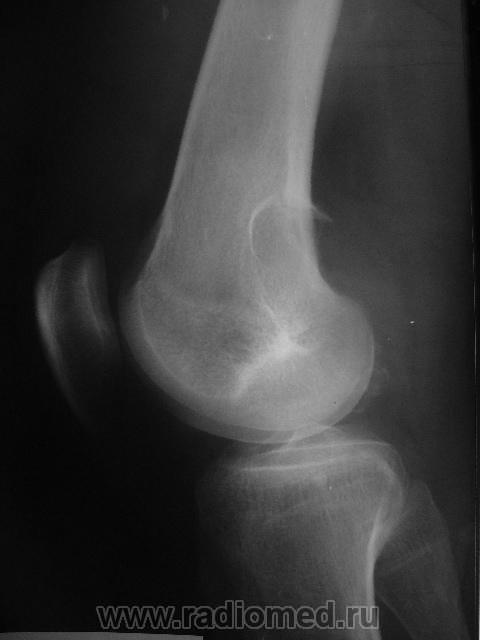

Здравствуйте, уважаемые коллеги! Сегодня в травмпункте принесли на описание снимки молодого человека 1984г.р. Травма, подвернул ногу. Жалобы характерные. Не наблюдался, не лечился. Прошу высказать мнение о характере патологии в метафизе бедренной кости.

Я склоняюсь к ГКО с кортикальным расположением, прорывом содержимого в мягкие ткани. А что думаете Вы? Т.к. снимок из травмпункта, поговорить с больным проблематично (я там совмещаю по вечерам).

На гигантоклеточную опухоль похоже, но не очень

Метафизарный кортикальный очаг фиброзной дисплазии. ИМХО.

какой красивый "козырек" по задней поверхности...

Расположение крупного очага деструкции эксцентрично (кзади) и вкрапления извести говорит в пользу солитарной хондромы, а местами нечеткие контуры ("скорлупа" теряется), "козырек" и  мягкоттканный компонент нацеливают на озлокачествление. Кроме того очень смущает структура прокс. эпиметафиза б/берц. кости. В любом случае, вижу прямые показания к активным действиям, начиная с биопсии.

И я за хондрому.

Спасибо за высказанные мнения. Интенсивная тень в проекции метафиза это артефакт на пленке. Больного я отправил на консультацию в специализированное учреждение, так что потеряться он не должен. Если узнаю результаты, то сообщу.